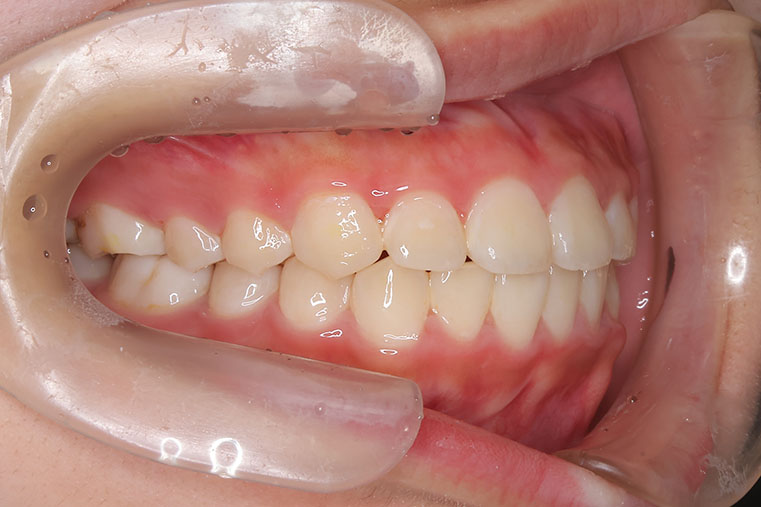

側方歯(犬歯、小臼歯)の生え変わりの時期。 前歯のがたつきを気にされ、小児矯正からの治療を希望されました。 お母様は、矯正治療経験済みですので、治療には前向きで早期治療の必要性を納得されていました。 小児矯正では、永久歯の生え変わるためのスペースを増加させ、がたつきを軽減させることを目的で行います。 残ったがたつきは、全ての永久歯が生え変わってから、本格矯正(マルチブラケット装置での治療)で改善しています。 比較的、叢生量は少ないため、本格矯正は非抜歯にて配列しました。

マルチブラケット 動的治療期間 2年6か月 調整回数16回 特に問題もなく、保定後も安定しています。